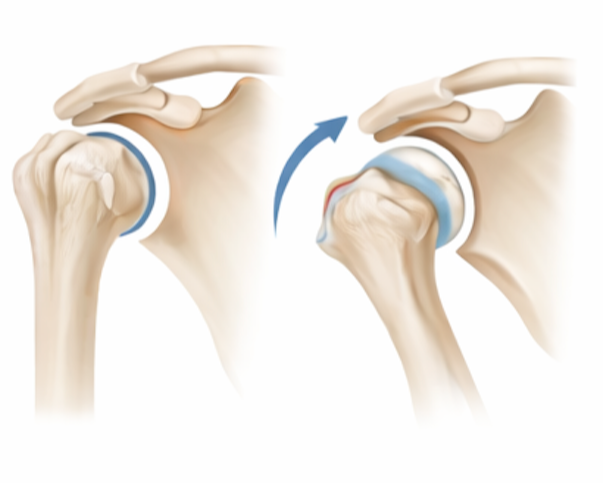

Shoulder Instability